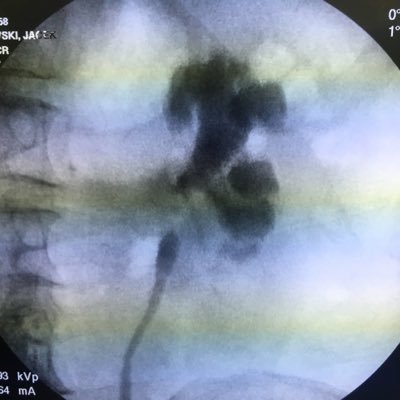

Today's endoscopic procedure brought us an Easter gift with a bow :)